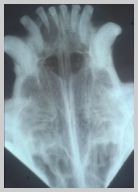

DV view of cat with fractures to

right mandible